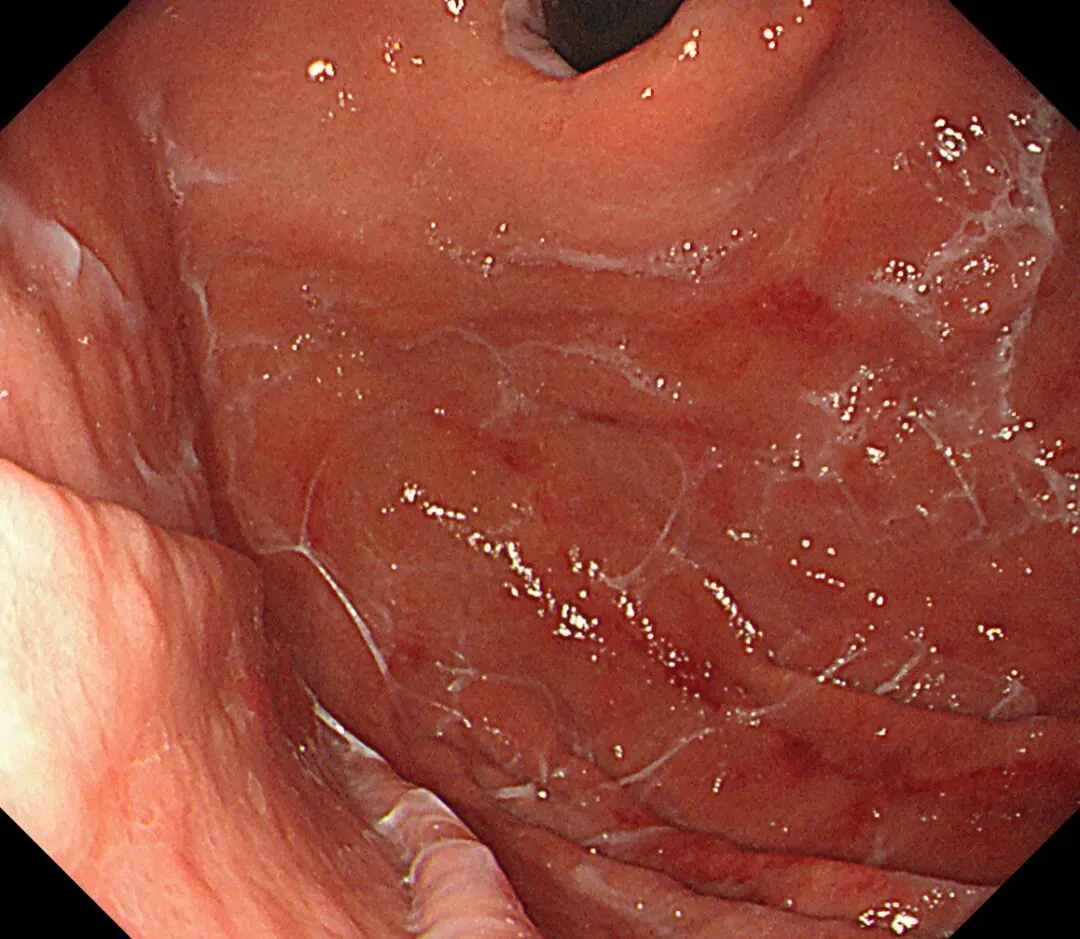

顽固性黏液(sticky adherent dense mucus):多呈灰黄色、黄白-乳白色,黏稠度高,附着于胃壁不易剥离,强行去除容易出血,也常有人称之为酒糟样固形物,多见于自身免疫性胃炎(AIG)进展期患者。

顽固性黏液case1,确诊为A型胃炎患者👇